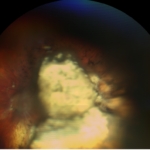

Mon fond d’oeil gauche : trouble avec énormément de cicatrices